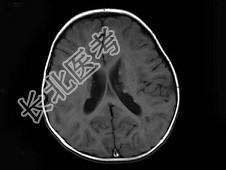

- 单项选择题男,1岁, 癫痫发作3次,智力反应低下, 头颅MRI扫描如图,最可能的诊断为 ( )

D、结节性硬化